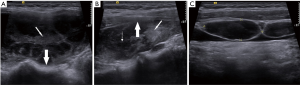

The dominant sonographic findings of PTL were large (average 4.8±1.7 cm, range 1.6–8.7 cm), solid (100%), ill-defined (81.5%) mass with echogenic strands (92.6%), posterior echo enhancement (85.2%) and without calcification (100%) (Table 2), while the dominant sonographic findings of ATC were large (average 5.8±2.1 cm, range 2.5–11.0 cm), solid (100%), ill-defined (100%) mass with macrocalcification or microcalcification (80%) (Table 2). PTL cases presented with diffuse type (25.9%) (Figure 1), nodular type (48.2%) (Figure 2) and mixed type (25.9%) (Figure 3). All ATC cases presented with nodular type (100%) (Figures 4,5). There is no significant difference in thyroid size, nodular size, margin, shape, echo texture, cystic change and vascularity on sonography between ATC and PTL groups (Table 2).

With regard to tumor-spreading patterns, in 15 patients with ATC, 13 patients had extra-thyroid extension into the surrounding soft tissue (Figure 4A), 1 patients invaded trachea, and 2 patients invaded jugular vein. In 27 patients with PTL, 14 patients had extra-thyroid extension into the surrounding soft tissue (Figures 2A,B,3B), 1 patients invaded trachea (Figure 1C).

A total of 25.9% (7/27) of PTLs presented with diffuse type, occupying entire thyroid without normal gland or most of the thyroid gland. Similar to the findings of the previous studies (20,26), all PTLs in our study are of B-cell lymphoma and predominantly of diffuse large-cell type, and the second most common histological type is MALT lymphoma. Most DLBCLs in our study showed nodular type (10/15, 66.7%). Compared to PTLs, all ATC cases were nodular type and limited to one lobe of thyroid, suggesting that PTL showed a propensity for more extensive disease at initial diagnosis. Plenty of ATC and PTL in our study showed direct invasion to the surrounding structures. Relevant literatures revealed that patients with ATC present with extensive local invasion at initial disease presentation in 15% to 50% of patients (27,28), and some research reported that invasion to the surrounding structures is rare in PTL (29,30). However, a few studies also reported PTL with aggressive appearance (31,32). Thus, the ultrasonographic features of local invasion were not specific enough to differentiate ATC from PTL.